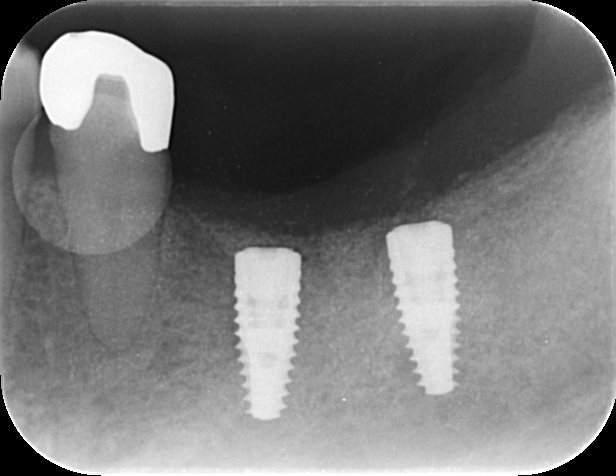

インプラント治療の症例4

レントゲン写真

- Befor

- After

| 年齢 | 50代・男性 |

|---|---|

| 主訴 | 部位:左下6番7番 主訴:左下奥歯腫れて痛い。 |

| 治療内容 | 左下6番抜歯、左下6番7番骨造成、インプラント埋入 |

| 治療費 | 合計:1,232,000円 ・内訳 診断料:55,000円 サージカルガイド2本:66,000円 GBR:110,000円×2本 埋入料:165,000円×2本 静脈内鎮静麻酔:77,000円 2次OPE:22,000円×2本 仮歯:55,000円×2本 上部構造(フルジルコニア):165,000円×2本 (2023年1月現在) |

| 治療期間 | 約8ヶ月 |

| 治療方針 | 元々支台歯に負荷がかかりやすいとされている延長ブリッジを抜歯し、1本単体でしっかりかめるようにインプラントを2本埋入した。骨吸収も進んでいたため、※GBR法で骨造成を同時に行った。 治療と並行して、全顎的な歯周病治療も行い、今後は歯周病が進行しないよう、こまめにメンテナンスに通っていただく。 |

| 特記事項 | ※1 GBR・・・骨再生誘導法。骨の高さや厚みを人工骨や人工膜などを使用し再生する方法 |

| 担当者所見 | 6番は歯根分割された被せ物が7番の欠損部との延長ブリッジとされており、強い咬合と歯周病も相まって負荷がかかり動揺し、歯として機能しなくなったため、抜歯となった。 |